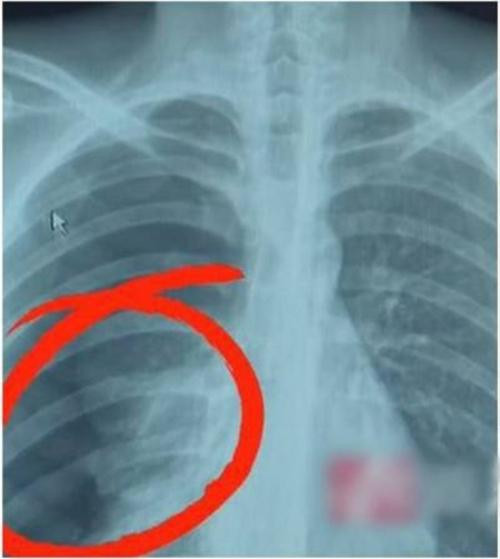

Đến sáng hôm sau, khi ngủ dậy, Wang không chỉ đau mà còn thấy khó thở nên gia đình vội đưa đi cấp cứu. Anh này kể cho bác sĩ nghe chuyện hát karaoke tối hôm trước, và nói rằng bị đau ở bên lưng phải suốt cả đêm. Bác sĩ chụp X-quang cho Wang và thấy anh bị tràn khí màng phổi, một tình trạng có thể đe dọa đến tính mạng, khi không khí bị tràn vào giữa phổi và thành ngực.

| Vì hát nốt cao mà Wang bị tràn khí màng phổi. Ảnh: OD. |

Các bác sĩ cho rằng, khi Wang căng mình lên cố hát các nốt cao thì anh đã gắng sức đến mức khiến những bóng khí ở phổi phải bị vỡ và phổi bị xẹp hẳn lại.